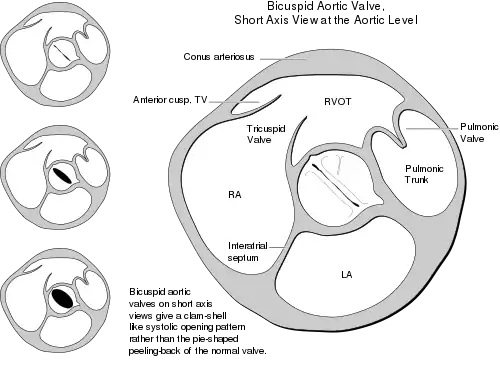

Bicuspid aortic valves may assume three different types of configuration:[20]

- "Real" bicuspid valves with two symmetric leaflets

- A tricuspid architecture with a fusion of two leaflets

- A tricuspid architecture with a fusion of three leaflets